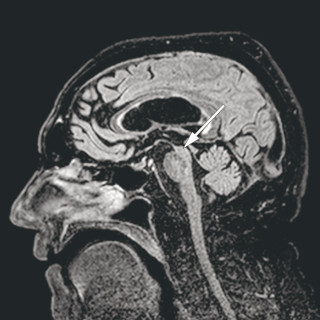

En mann i 70-årene ble henvist hematologisk poliklinikk grunnet redusert allmenntilstand og anemi. Blodprøver viste hemoglobin 9,7 g/dl (13,4–17,0), gjennomsnittlig cellevolum i de røde blodcellene (MCV) 115 fl (82–98), leukocytter 3,0 · 10 9/l (3,5–11,0), trombocytter 187 · 10 9/l (145–348), folat 7,2 nmol/l (> 8,0), kobalamin 693 pmol/l (175–700) og ferritin 831 µg/l (34–300). Tilstanden ble oppfattet som megaloblastisk anemi på grunn av folatmangel, og man startet med folatbehandling. Kontroll etter to måneder viste vedvarende anemi med hemoglobin 9,4 g/dl. Benmargsutstryk med May-Grünwald...